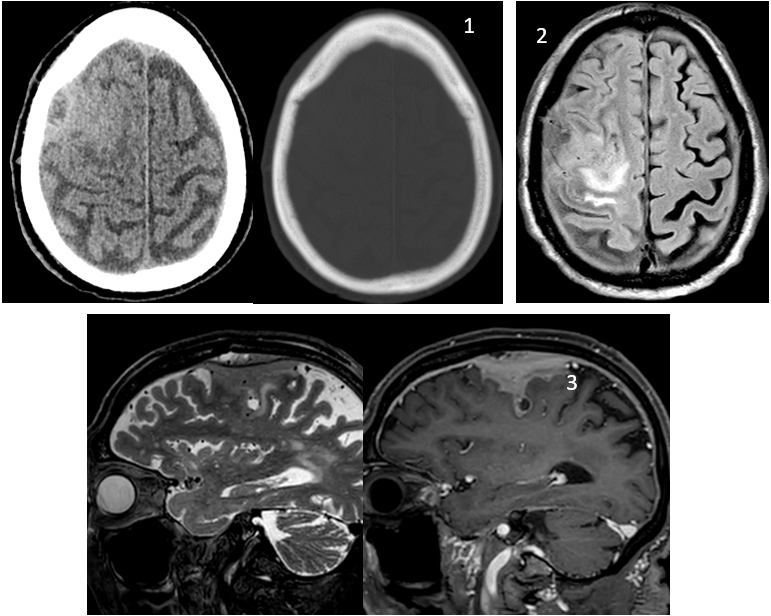

1. TC simple: anomalía extraaxial frontal derecha hiperdensa, sin erosión ósea

2. RM axial FLAIR: alteración de señal hiperintensa en surcos frontales y lesión heterogénea cortico-subcortical. Engrosamiento e hiperseñal difusa dural bilateral

3. RM sagitales T2 Y T1Gd lado Dcho: lesión epidural sin afectación ósea. Afectación de espacio subaracnoideo con señal intermedia en T2 y captación intensa postcontraste i.v. Captación difusa dural en la convexidad de ambos hemisferios